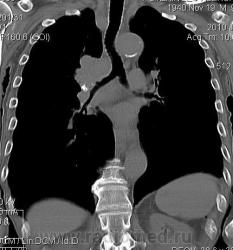

Мужчина 69 лет, с последствием ОНМК находился в доме-интернате для инвалидов. В анамнезе пневмония справа и исходом в пневмосклероз. ФЛГ не проходил 1.5 года. Анализы: СОЭ 20 мм/ч, остальное - без особенностей. Поступил в неврологическое отделение с диагнозом: повторное ОНМК. Невролог заподозрил метастазы головного мозга, направил на рентгенографию легких. После выявленых изменений в правом легком, пациент направлен на КТ головного мозга и грудной полости. От контрастирования и бронхоскопии категорически отказался.

По поводу подозрения на туберкулез пациента в прошлом нодократно проверяли, исключили. ФЛГ архива у меня нет. Все только со слов пациента. Кальцинаты в корне массивные. Трудно сказать, откуда опухоль (если это не конгломерат лимфоузлов!) плотностью 35 ед.Н - то ли из вехнедолевого бронха, который имеет культю 0.4 см и заканчивается выпуклым контуром, но при этом сохраняется воздушность почти всей доли; то ли периферический с центром в прикорневой зоне и вторичным прорастанием ВДБ. К сожалению забыла про снимок легких, на днях выставлю. Я первоначально считала периферический (верхушка, на фоне пневмосклероза) с мтс средостения. По плотности на верхушке узелок 5 ед.Н, только поэтому засомневалась, где же первичный. Лимфоузлы средостения множественные, до 2 см. Кроме того, на верхней стенке правого главного бронха есть мелкое образование такой же 35 е.Н плотности, то ли аденома, то ли прорастает... Без бронхоскопии - только гадать

это периферический рак S2 в/доли правого легкого с мтс во внутригрудные л/узлы.

А тут нечего гадать - данную демонстрацию можно поместить в учебник: узловое образование, с бугристыми, лучистыми контурами, связаное с плеврой, "дорожкой" к корню, перифокальной инфильтрацией. Корень расширен полицикличен за счет конгломерата увеличеных бронхопульмональных, трахеобронхиальных и бифуркационных л/узлов, значительно сдавливающих в/долевой бронх, с нарушением вентиляции в/доли.

Центральный рак ВДБ справа с мтс в л/узлы паратрахеальные нижние, верхние справа, БФ. МТС в головной мозг. А про печень мало сканов

Мне кажется в 6 сегменте печени мтс + еще мтс поражение левого надпочечника вероятнее всего. Мтс в нижние паратрахеальные (с обеих сторон)+бифуркационные л/у. Поражения верхних паратрахеальных не вижу (на коронарах), аксиалы - не показыны сканы выше верхнего края дуги аорты, так что я бы не говорил про поражение верхних медиастинальных лимфоузлов (хотя тут это уже не принципиально) + мтс в головной мозг. А так - центральный рак правого легкого.